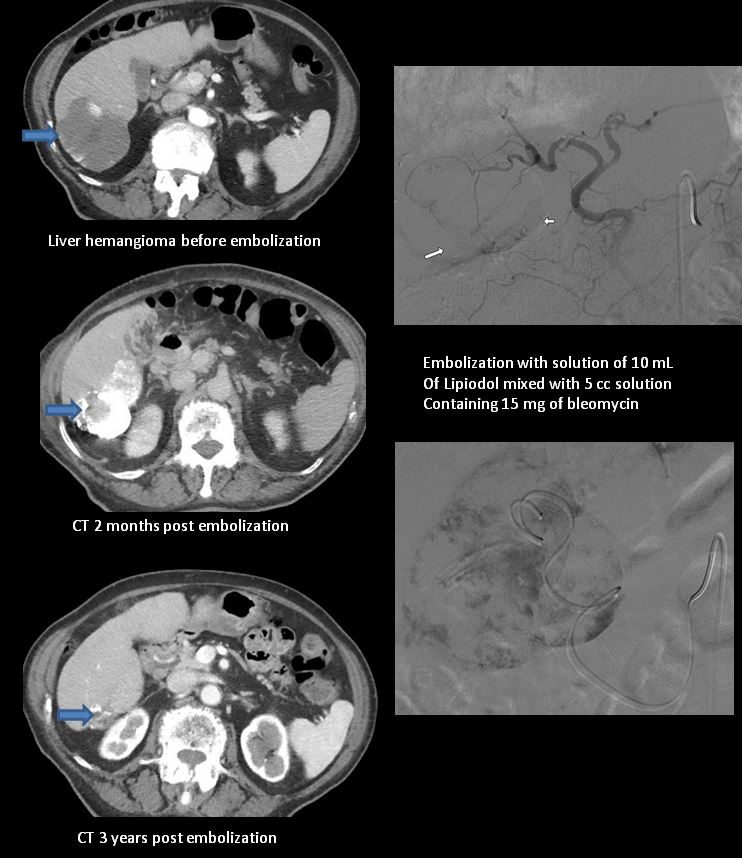

Um tratamento não cirúrgico cada vez mais utilizado é a embolização do tumor. O radiologista passa um cateter por uma veia, que chega até o vaso que fornece sangue para o hemangioma. Então o radiologista pode ou não injetar uma substância esclerosante (para “queimar”), seguida de outra substância (como pedacinhos de espuma) que entope o vaso. Isso faz com que o hemangioma regrida com o tempo.